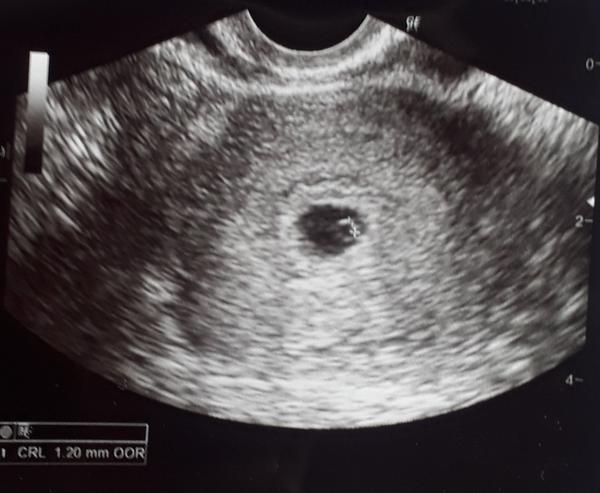

@katkaholiova super,je to tam. Nech len silnie 👍

@katkaholiova nieco sa tam crta, tak drzim palce nech zostane a silnie 😊 Pepino dost slabo ukazuje. Skus mama test, ten ukaze // pekne 😊